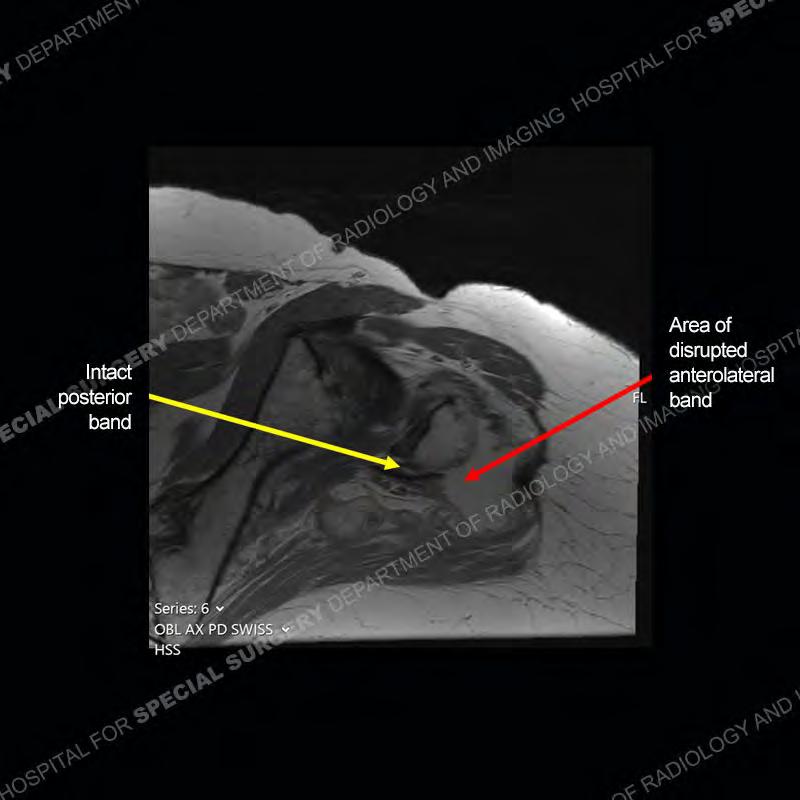

The radiograph is not particularly contributory in this case. The MRI demonstrates markedly abnormal architecture of the gluteus minimus and anterolateral band of the gluteus medius. Portions of the tendons are high signal, portions are highly attenuated, and portions are disrupted. A large, complex fluid collection is present in the adjacent soft tissue.

Not as much of a diagnostic dilemma as many of the other cases shown but just a nice example of the pathology seen of the gluteal tendons and a cause of trochanteric pain. Although, frequently thought of in isolation, trochanteric bursitis or bursal thickening is much more commonly a reactive change to underlying pathology of the subjacent gluteal tendons. The gluteus medius is divided into a posterior band and an anterolateral band. Tendinosis and partial tearing very commonly will involve the gluteus minimus and especially the more posterior fibers and then propagate into the anterior lateral band of the gluteus medius. Involvement of the posterior band of the medius is much less common and engenders a marked degree of functional impairment.